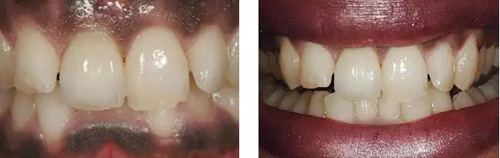

圖1、該病例顯示了厚齦生物型和中弧線形齦乳頭形態(tài)。右上中切牙由于牙根縱裂而需要拔除。由于該患牙伸長,使得軟組織量垂直向增加。牙齦色素沉著是個(gè)美學(xué)挑戰(zhàn)。

圖10、剛植入種植體當(dāng)天的情況(左)和植入種植體1年時(shí)的情況(右)。

圖11、牙冠戴入1個(gè)月以后。軟組織外形良好,形成了良好的弧線形牙齦形態(tài)而沒有瘢痕。保持了原有的色素沉著的顏色和形狀。

圖12、種植術(shù)后1年顯示良好的美學(xué)效果。